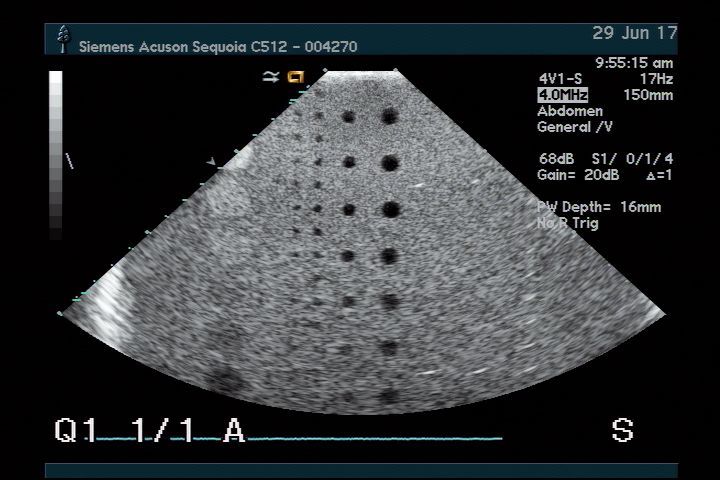

The Acuson 4V1 for Sequoia 512 Ultrasound Transducer is renowned for its superior imaging capabilities. It utilizes advanced technology to provide clear and detailed images, which are crucial for accurate diagnoses. Because of its exceptional resolution, medical professionals can identify conditions more efficiently, helping patients receive timely treatment. This transducer truly enhances diagnostic confidence.

This ultrasound transducer boasts versatility, making it suitable for various applications in healthcare. It can be used in obstetrics, cardiology, and general imaging, which means healthcare providers can rely on it for multiple patient needs. This adaptability is beneficial, as it reduces the need for multiple devices. As a result, clinics can maximize their resources effectively.